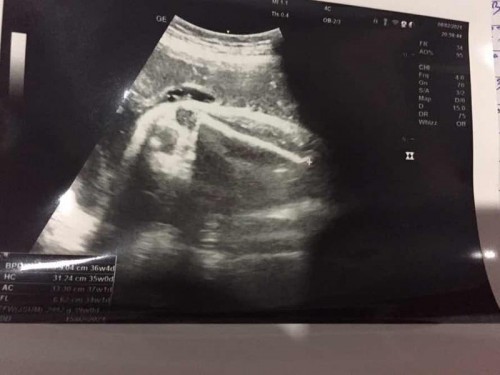

รูปแรกระหว่างข้อพับ รูปสองต้นขา รูปสามหน้าท้อง

ไม่ใช่รูปนี้ค่ะ รูปนี้กระดูกต้นขา

อายุครรภ์เยอะแล้วดูเพศยากค่ะ